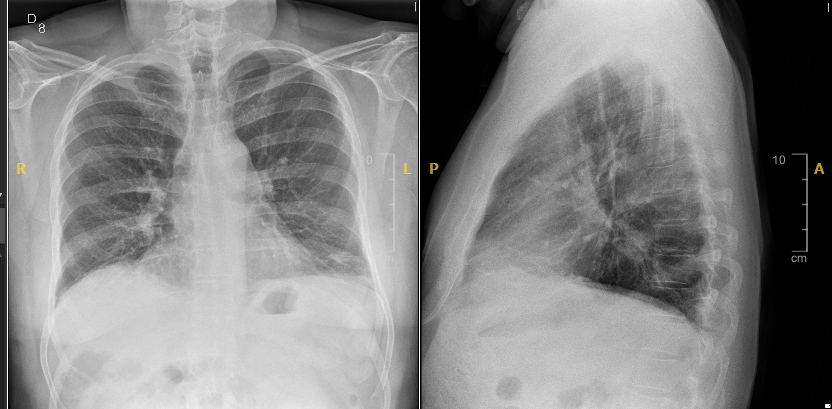

Acude a consulta por edema pie derecho de 1 mes de evolución y disnea de 1 día con dorsalgia derecha. Afebril. Valorado en Hospital hace 48 h por dorsalgia, realizada Rx Lumbar y tratado con AINE.

TA:142/75, 73 lpm FR:18rpm, SatO2:99% aire ambiente con caida de la saturación en decubito supino hasta 94%. Sin soplos ni ruidos respiratorios patológicos. Edema pie derecho con fovea hasta tobillo.

Eco Pulmonar: slidding pleural presentwe, lineas A, no aprecio lineas B ni derrame pleural.